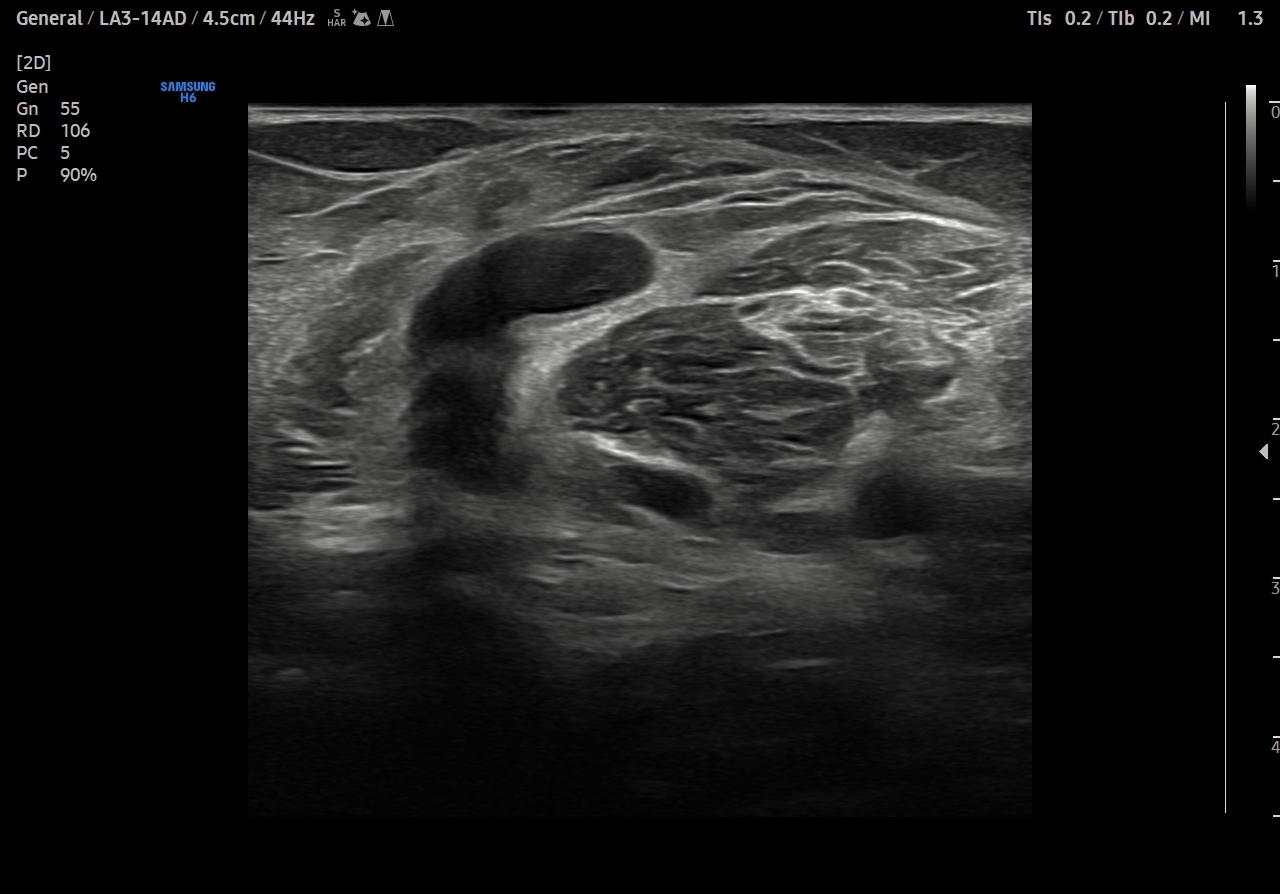

Se explora cara anterior, lateral y medial de rodilla sin hallazgos significativos. En cara posterior se explora el hueco poplíteo donde se visualiza en corte transversal una estructura hipoecoica con la base, el cuello entre el tendón del semimembranoso y el tendón de la cabeza medial del gemelo interno y el cuerpo. Sin signos de complicación. Permeabilidad del sistema venoso profundo.

Quiste de Baker.